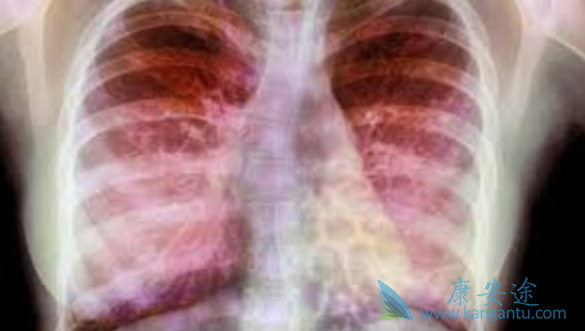

很多人常常听说肺癌、肺炎、肺结核之类的肺部疾病,却很少听说肺部纤维化,那么什么是肺部纤维化?按照专业解释来讲,肺部纤维化并不算是一种疾病,一般被称为一种病理性改变,而与肺部纤维化直接相关的疾病是“间质性肺病”。比较通俗易懂的解释来讲,肺部纤维化可以比喻为肺部发生病理性改变之后出现的“疤痕”。肺部纤维化的病人多数会因为呼吸困难、咳嗽不断、咯血而就诊,确诊之后的肺部纤维化病人可能会根据引发原因而被安排到呼吸科进行治疗。那么肺部纤维化恶毒患者该如何治疗呢?

肺部纤维化